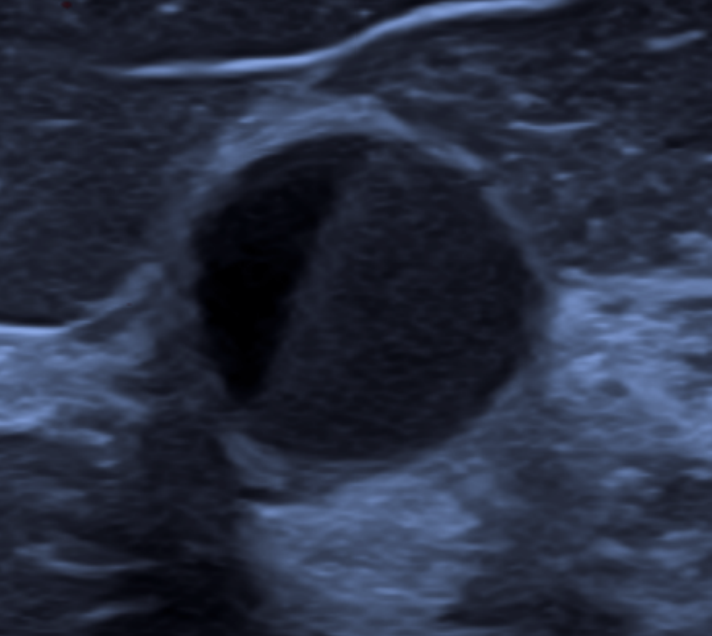

BI-RADS US® (2025) – Descrição e Classificação de Achados Mamários

Ferramenta educacional para descrever sistematicamente achados mamários à ultrassonografia, segundo o BI-RADS US (ACR, edição 2025)